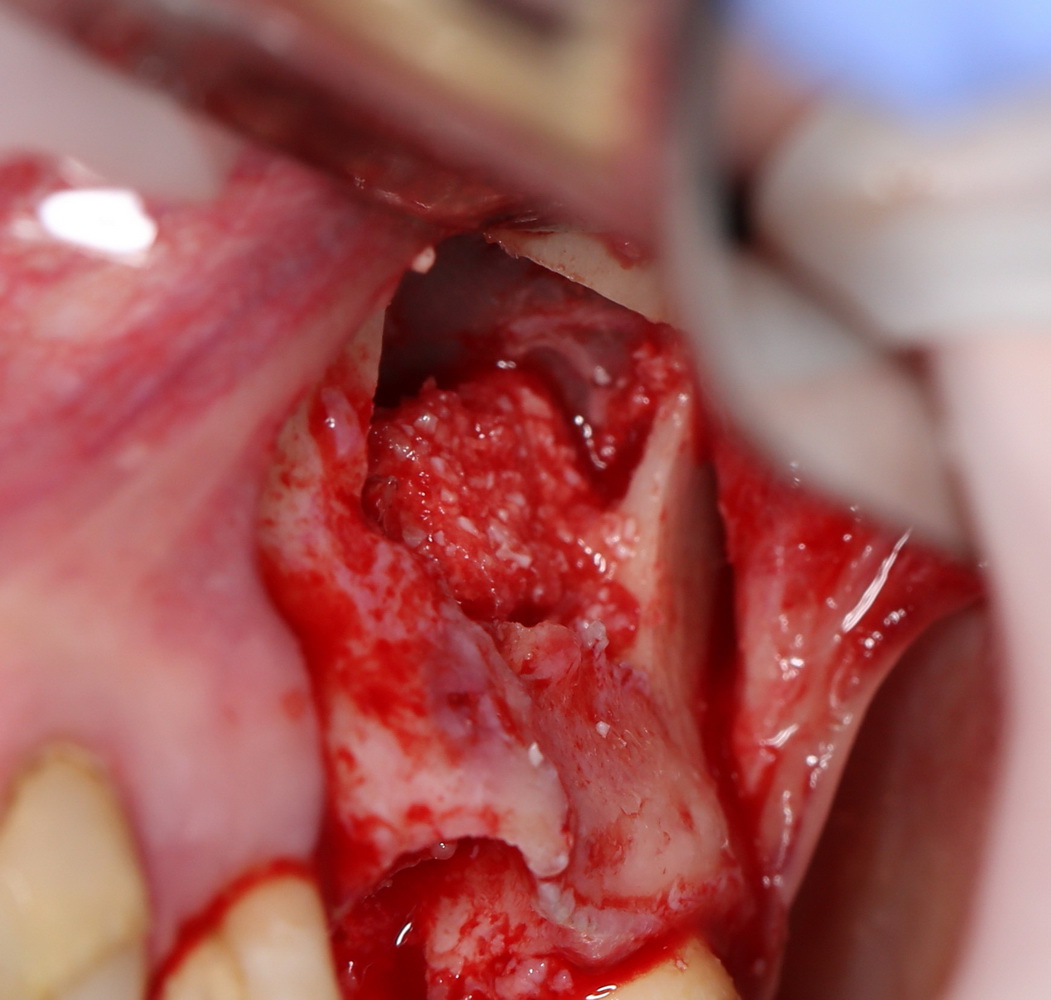

Остеопластические операции: факторы успеха. Часть II.